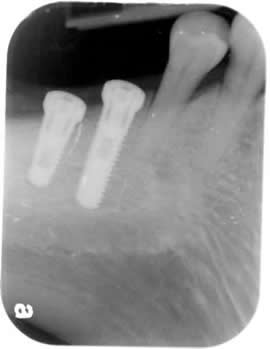

Two big molars are missing at the back. This is again a common situation. Two root-form implants are placed. Two crowns are restored onto the implants. Why wear denture? |